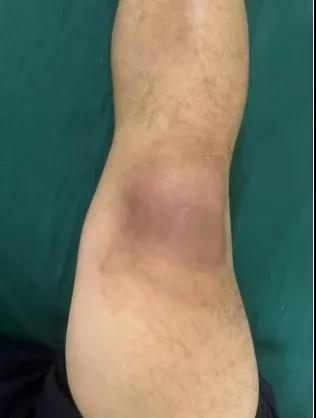

近日,漯河醫(yī)專二附院(漯河市骨科醫(yī)院、漯河市立醫(yī)院)手顯微外科(骨四科)李俊明主任團(tuán)隊(duì)?wèi)?yīng)用清熱解毒、拔毒生肌類中藥(骨炎膏)外用結(jié)合抗生素成功治愈一例膝關(guān)節(jié)外傷后軟組織感染病人。

患者,以“外傷致右膝紅腫、疼痛20余天”為主訴就診,20余天前,因騎電車摔傷右膝關(guān)節(jié),致使出現(xiàn)右膝腫脹、疼痛、活動(dòng)受限,在當(dāng)?shù)蒯t(yī)院給予消腫、止痛治療效果差,繼而出現(xiàn)膝關(guān)節(jié)紅腫熱痛癥狀,門診給予滑膜炎片及消腫止痛藥物治療癥狀未見好轉(zhuǎn),慕名前來我院手顯微外科住院。入院當(dāng)天即給予中藥外敷(骨炎膏),穿刺膿性分泌物送細(xì)菌培養(yǎng),給予廣譜抗生素治療(細(xì)菌培養(yǎng)未出)。

中藥外敷(骨炎膏)主要適用于局部紅腫熱痛,四肢血栓形成、靜脈炎等,具有清熱解毒,拔毒生肌的作用。

中藥外敷骨炎膏給藥直接作用于病灶,彌補(bǔ)了單純口服藥物局部濃度不足的缺陷;同時(shí),中藥外敷與抗生素的系統(tǒng)性抗感染形成"靶向-全身"雙重干預(yù),可顯著縮短療程并降低耐藥風(fēng)險(xiǎn),更為中西醫(yī)結(jié)合治療軟組織感染提供新的思路。(盧 闖 賈煒煒 劉 旭 袁錦鈺)